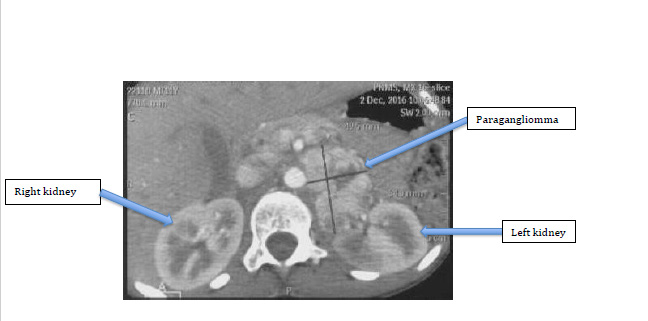

Auscultation noted fast and irregular heart sounds with no abnormal murmur. Auscultation of the arterial axes and the rest of the exam were normal. The blood count was normal as well as serum creatinine and C reactive protein. The urinary metanephrine dosage found a Noradrenaline level = 9930nmol/l or 1678ug/l (normal between 0 to 80 ug/l). The electrocardiogram recorded junctional tachycardia at 150 rates per minute (Figure 1), left ventricular hypertrophy, circumferential epicardial ischemia. Cardiac ultrasound found no coarctation or anomalies in venous return. Moderate left ventricular hypertrophy with mild systolic dysfunction (left ventricular ejection fraction at 50%) was found due to global hypokinesia. The disposition of the coronary arteries was normal. As part of the etiological research of this paroxysmal hypertension associated with palpitations and abdominal pain, an abdominopelvic CT scan was requested and this one revealed a retro peritoneal tissue process measuring 69x 50x34 mm (Figure 2&3) localized at hilar renal left. After dye injection, the mass was well filled and heterogeneous. Moreover, in the presence of junctional tachycardia, we take the opinion of a rhythmologist who concluded that there was junctional tachycardia with atrioventricular dissociation. The combination of an alpha blocker (Cardox 4mg/day) with Sotalol 30mg/m2 and 30mg of verapamil was recommended, which allowed good control of its blood pressure and a decrease of the heart rate. The diagnosis of paraganglioma was retained and the patient was sent to pediatric surgery staff for the management of this tumor.

Figure 2 Ct scan Showing Retro peritoneal tissue process measuring 69x 50x34 mm localized at hilar renal left intensified and heterogeneous at arterial time with foci of necrosis.

Figure 3 CT scan peritoneal tissue process localized at hilar renal left intensely intensified and heterogeneous at arterial time with foci of necrosis.